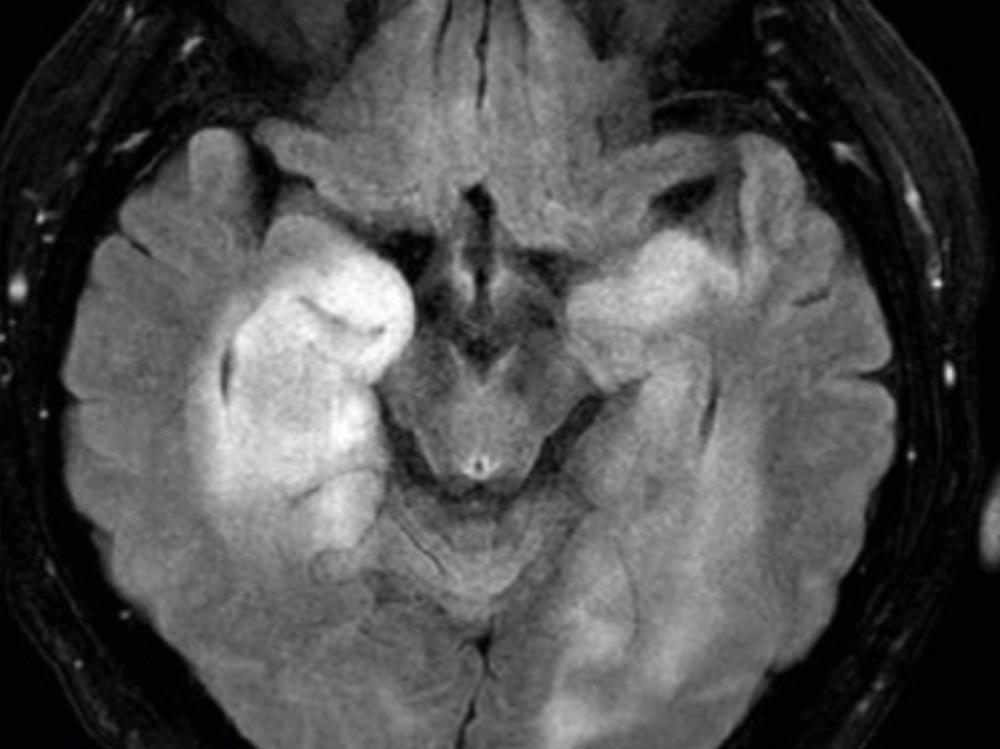

Kia ora, my name is Jay, and I’m reaching out with a heavy heart but also with hope. Recently, I was diagnosed with astrocytoma (brain tumors) that require surgery to remove it before it becomes malignant. This is going to be one of the hardest challenges of my life, both physically and emotionally, and while I’ve always tried to stand strong and handle things on my own, this is something I can’t face alone.